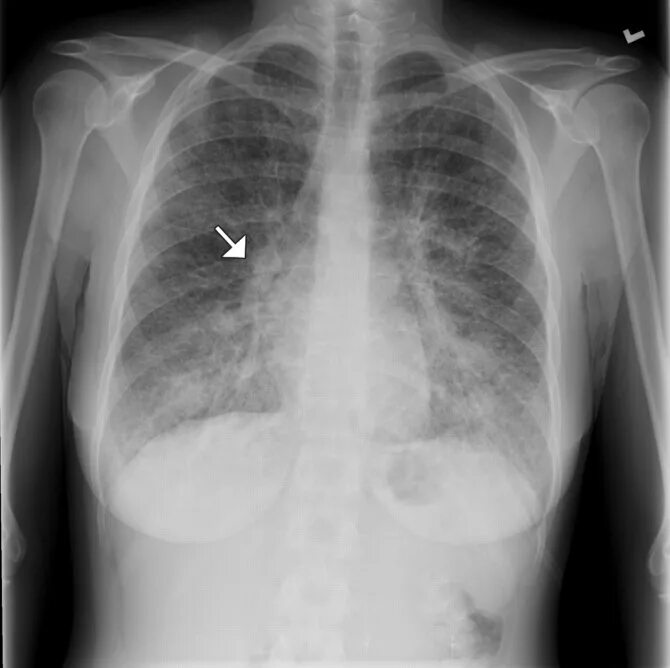

Метастазы в лимфоузлах легких